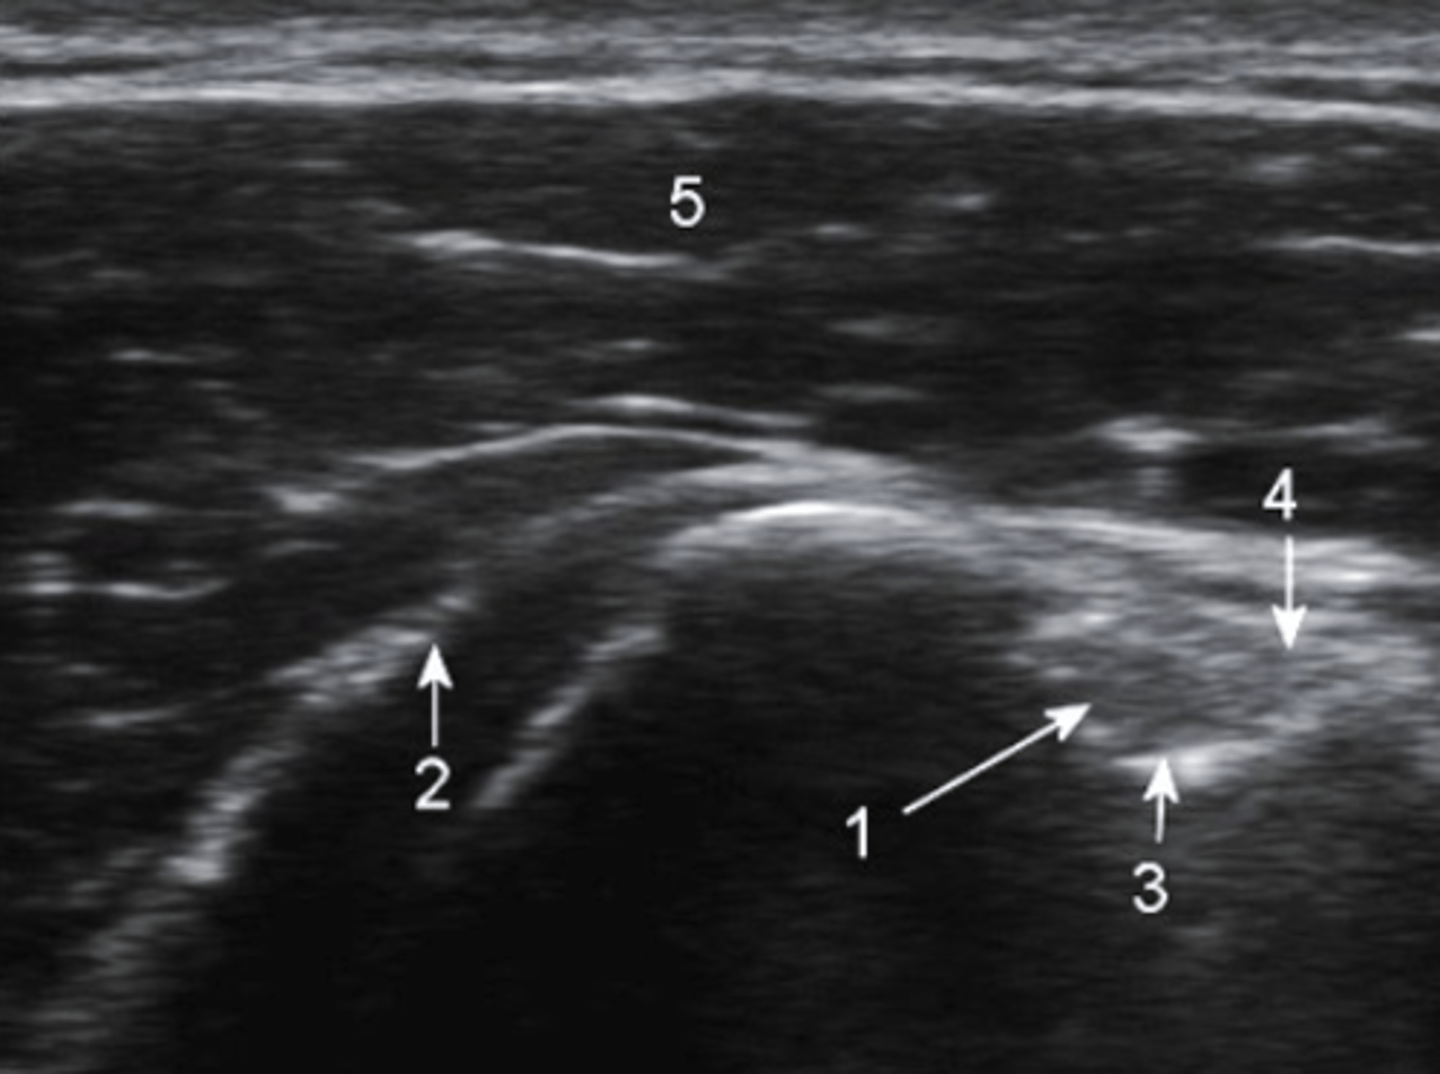

Ultrasound, partial tear

What type of imaging is this and what is identified by the white arrows?

a. CT scan, fracture

b. Ultrasound, partial tear

c. Ultrasound, Swollen Bursa

d. T2 MRI, torn ligament

ultrasound, transverse

What type of imaging is this and how is it being viewed?

a. ultrasound, longitudinal

b. T2 MRI, frontal

c. CT Scan, axial

d. ultrasound, transverse

ultrasound

what type of imaging is shown here?

a. fluoroscopy

b. ultrasound

c. bone scan

d. CT